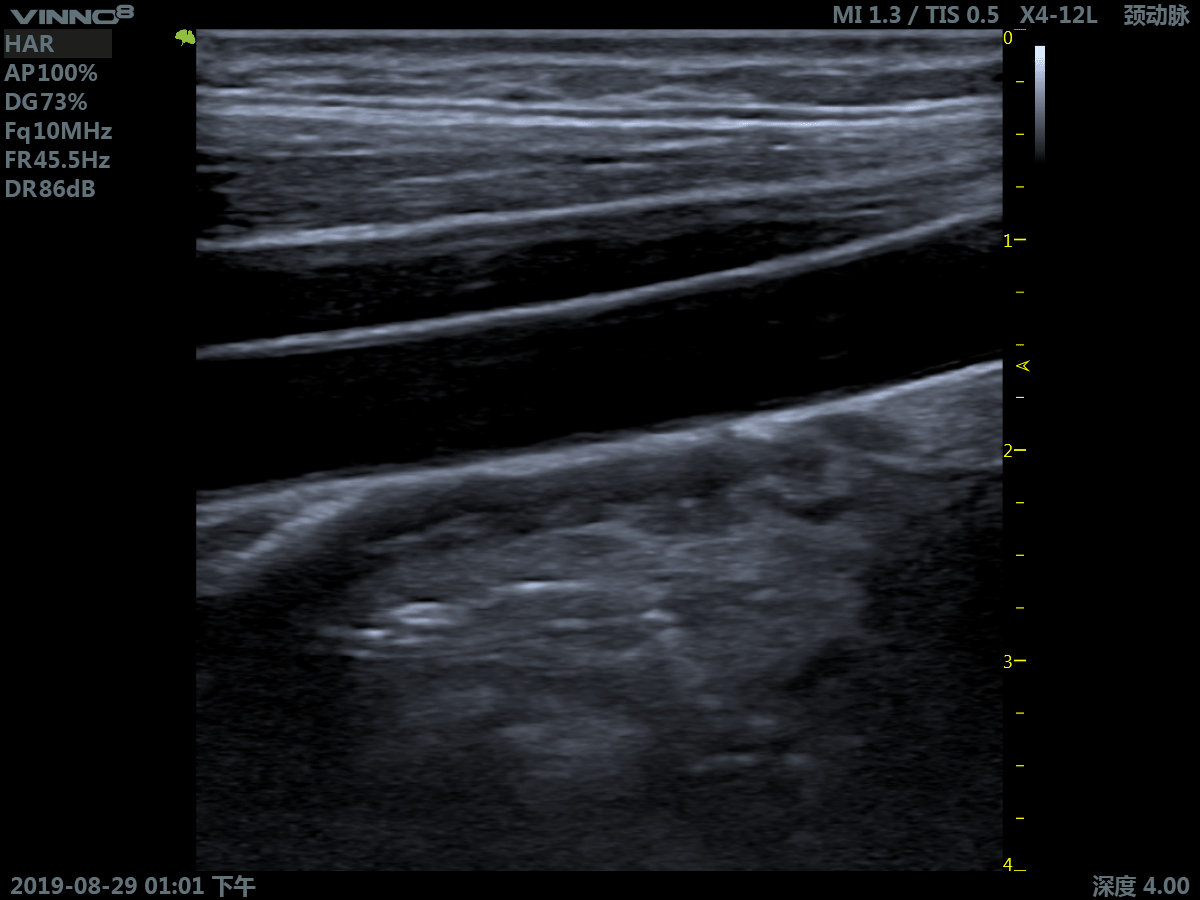

Портативный ультразвуковой сканер VINNO 8

Преимущества портативного УЗИ аппарата VINNO 8

- инновационная платформа RF обеспечивает суперчистое изображение в результате сверхвысокой скорости обработки данных

- сверхвысокая частота (до 23 МГц на линейном датчике)

Клиническое применение:

- периферические сосуды